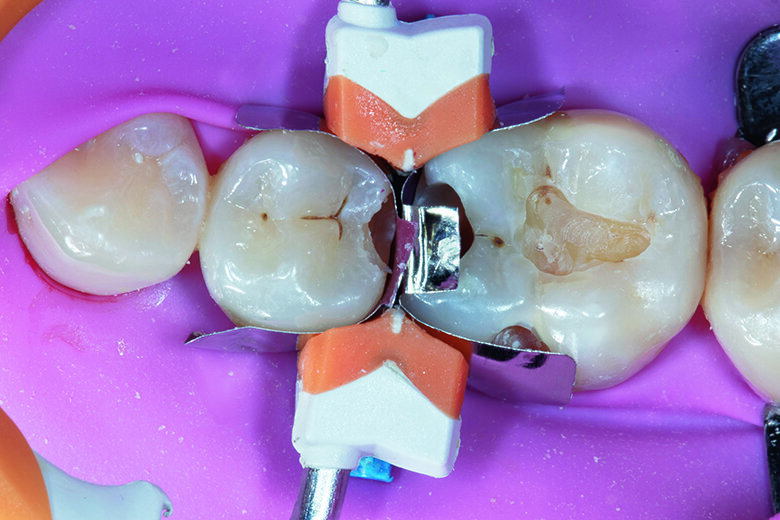

Prior to caries removal, proper quadrant isolation was done with placement of rubber dam and pre-wedging with Garrison small FXBL wedge.

Tip: Pre-wedging creates momentary tooth separation to help achieve a more accurate proximal seal with ideal contact after placement of the final restoration and the teeth return to their original position. In addition, it helps to protect the rubber dam when removing the caries in the cervical area.

Caries removal was completed with a blue stripped high speed small round bur followed by slow speed round carbide bur. Caries detection dye was applied to ensure complete removal of active decay. Old composite was removed from occlusal and buccal pit area of tooth #46. For tooth #45, decay was initially removed without touching the occlusal surface, however as the marginal ridge area was left with very thin structure, the proximal box was later extended to the occlusal surface (C-shaped preparation) to avoid excessive stress that could lead to restoration failure (Fig. 2).

Fig. 2. Pre-wedging with removal of active decay on teeth #45, 46.